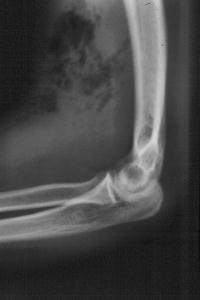

This patient presented with signs of systemic sepsis, antecubital swelling, pain and crepitation 36 hours after injecting but missing an antecubital vein.

Xrays confirmed multiple gas pockets in the soft tissues. The patient was treated with broad spectrum antibiotics, emergency debridement, delayed closure, and was free of infection until lost to followup three weeks later.